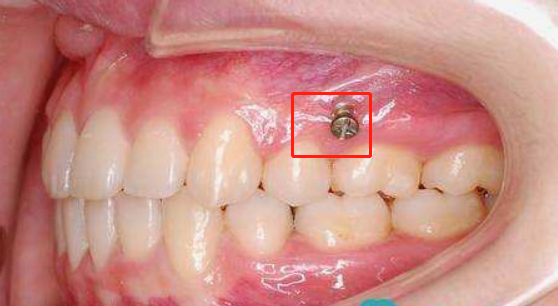

骨釘,顧名思義,是一種外形十分像釘子的種植釘,是放置在牙骨上方一個迷你的"釘子"。

它體積的小,好植入,近年來,逐漸成為正畸科常用的正畸輔助工具。

骨釘植入屬于一個小手術(shù),在整個過程中,患者會感到一定的侵入性,一般情況下,醫(yī)生會局部上麻藥后,將骨釘植入進(jìn)去。